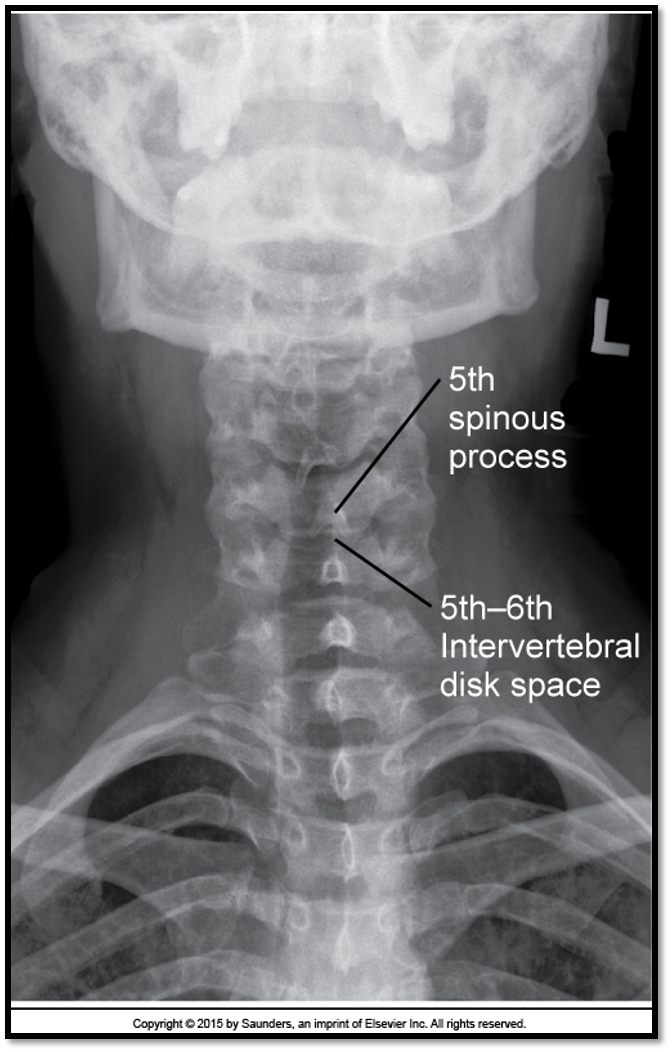

AP Axial Cspine criteria

A

• occipital bone and mandible lined up (extension)

• spinous process midline (rotation)

• open vertebral discs (angle)

• all of C3 is visible

• need to lift the chin more

• all of C3 is demonstrated